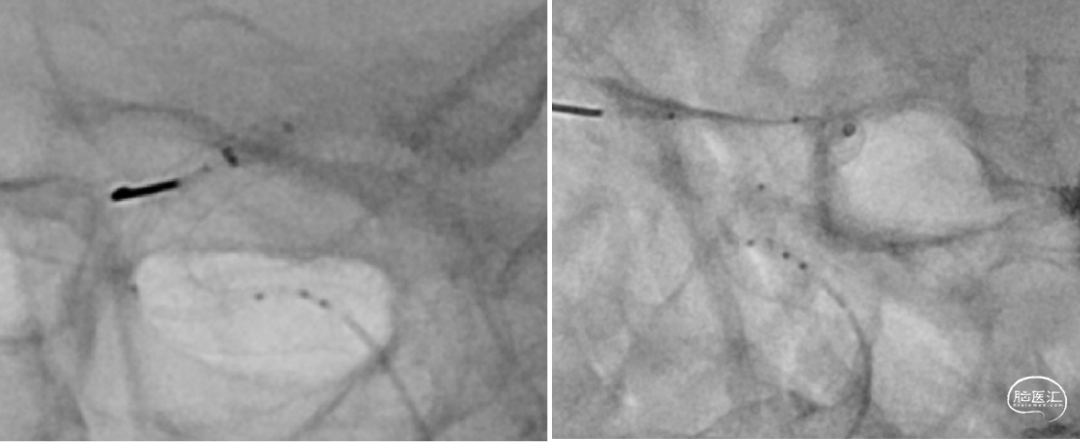

通桥微导丝导引支架管到位

支架鞘置入Y阀高压快速水化

支架释放过程(4倍速),重点是过弯推拉。

支架精显